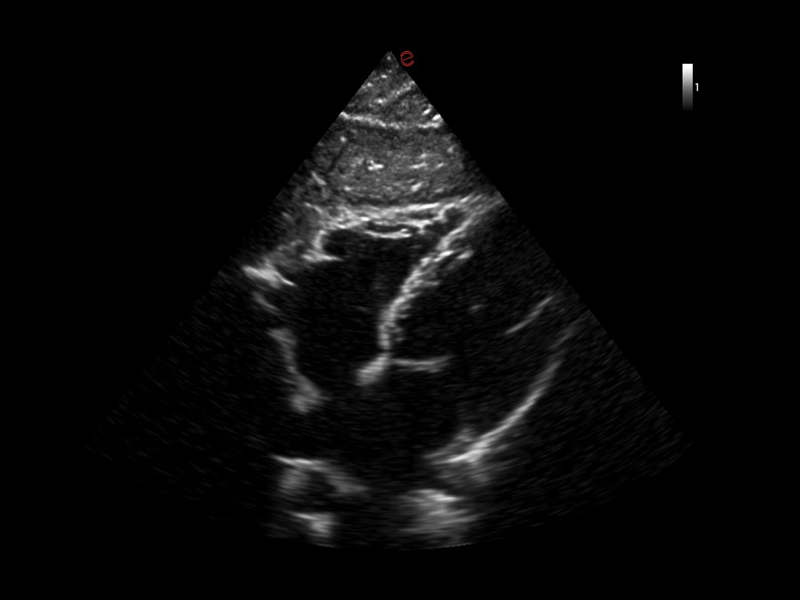

MyLab™X1 Go - Cardio fast

MyLab™X1 Go - Cardio fast